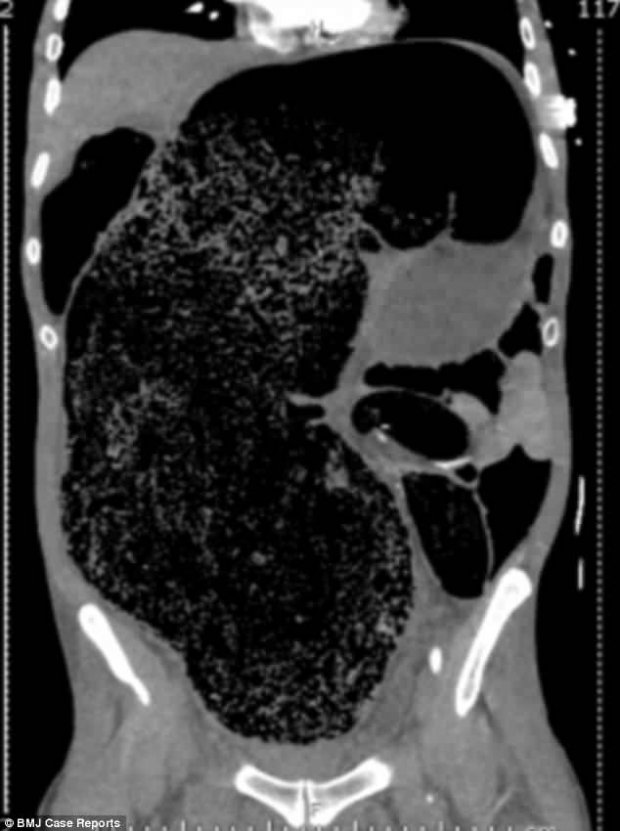

Ảnh chụp CT cho thấy lượng phân khổng lồ tích tụ trong khoang bụng bệnh nhân. |

Theo chẩn đoán của các bác sĩ, khối lượng phân lớn tích tụ trong cơ thể này là nguyên nhân chính dẫn tới tình trạng đau đớn của bệnh nhân, bởi nó chèn ép các nội tạng xung quanh của người đàn ông như tăng áp lực lên dạ dày, làm tắc các mạch máu lưu thông xuống chân, làm tổn thương thận.